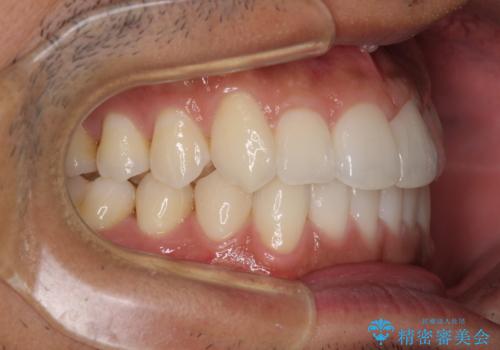

前歯のデコボコを治したい インビザライン矯正治療

- 前歯のデコボコを治したいとのことで来院された患者様です。

上下顎ともに歯列全体の後方移動とIPR(歯と歯の間を削る)によってデコボコが解消するように設計し、インビザラインにより治療を行うこととしました。

毎日22時間以上しっかりとマウスピースを装着していただいたので、スムーズに治療が進みました。歯と歯の間を削ることでうまくスペースコントロールでき、1年強で終えることができました。